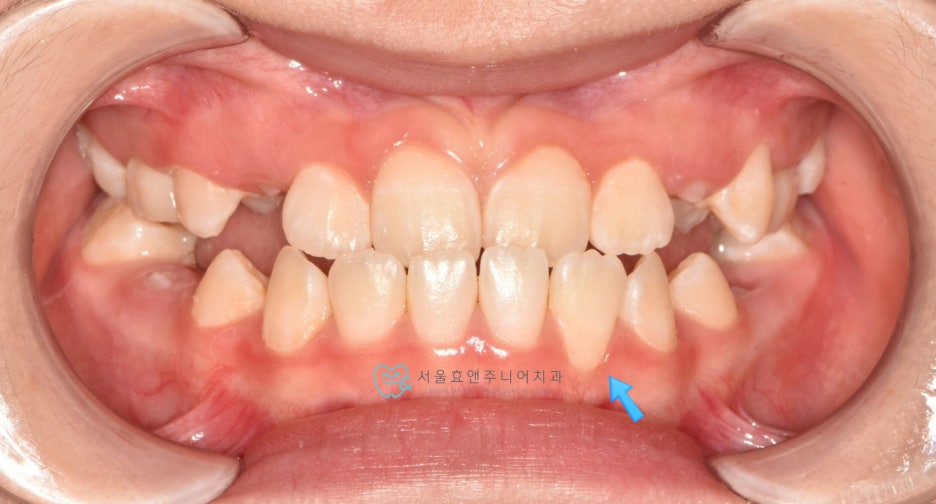

초진사진입니다

초진사진입니다. 11세 5개월 환아로, 반대교합을 보이고 있습니다. 반대교합으로 인해 치아가 부딪혀 치은퇴축(잇몸이 내려감)도 보이고 있네요.(화살표)